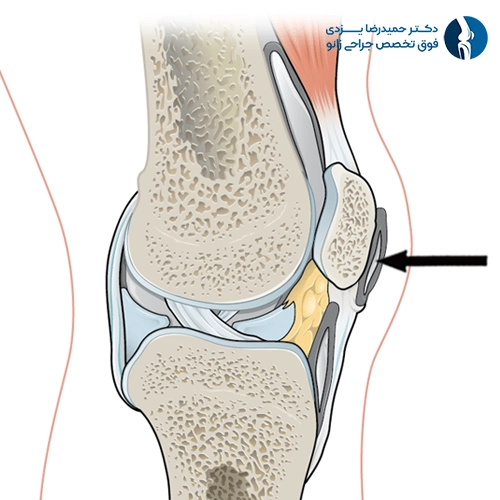

بورسیت پسکشککی (Infrapatellar Bursitis)

در این نوع، کیسه بورس در زیر استخوان کشکک ملتهب میشود. این بورس در بین تاندون پاتلار و استخوان درشتنی قرار دارد و به حرکت روان زانو در حین خم و راست شدن کمک میکند. التهاب در این ناحیه اغلب بهدلیل پرشهای مکرر یا فشارهای عمودی شدید ایجاد میشود، از اینرو به آن «زانوی کشیش» یا Clergyman’s knee نیز میگویند.

علائم شامل درد در قسمت جلوی زانو، کمی پایینتر از کشکک، و تورم موضعی است. گاهی ممکن است بهخاطر شباهت علائم با تاندونیت پاتلار اشتباه گرفته شود. درد در حالت نشستن طولانیمدت یا بالا رفتن از پلهها نیز شایع است.

درمان معمولاً شامل اجتناب از فعالیتهای تشدیدکننده، استفاده از زانوبند، داروهای ضدالتهاب و تمرینات فیزیوتراپی برای تقویت عضلات اطراف زانوست. در موارد مقاوم، ممکن است تزریق کورتون انجام شود.